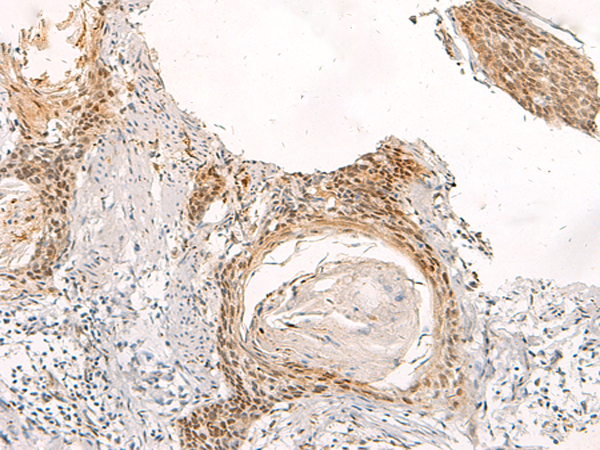

分类: 科研抗体货号: P12415别名: EVA; PDS; DFNB4; TDH2B应用: IHC反应种属: Human, Mouse, Rat